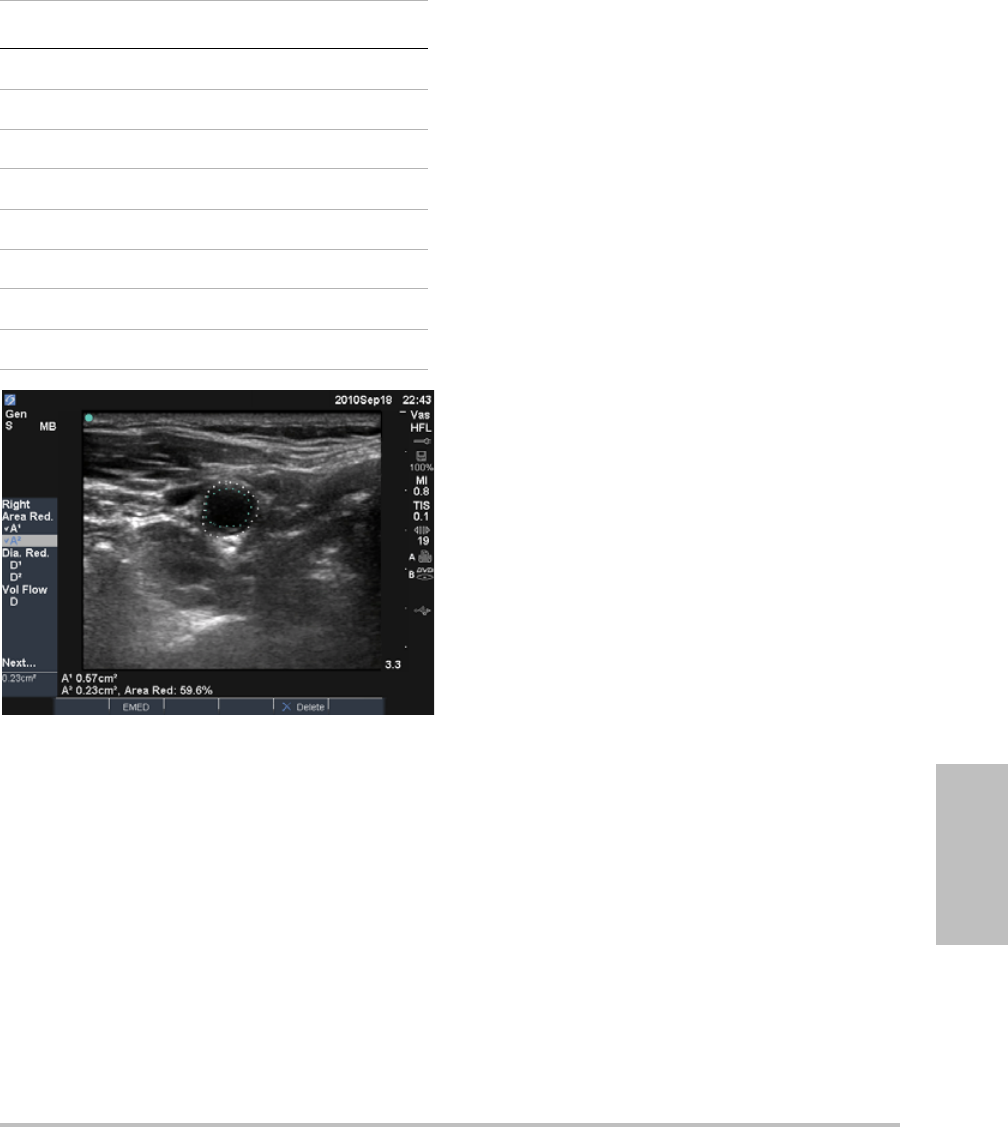

EMED calculations ..............................................................................................46

Percent reduction calculations ......................................................................46